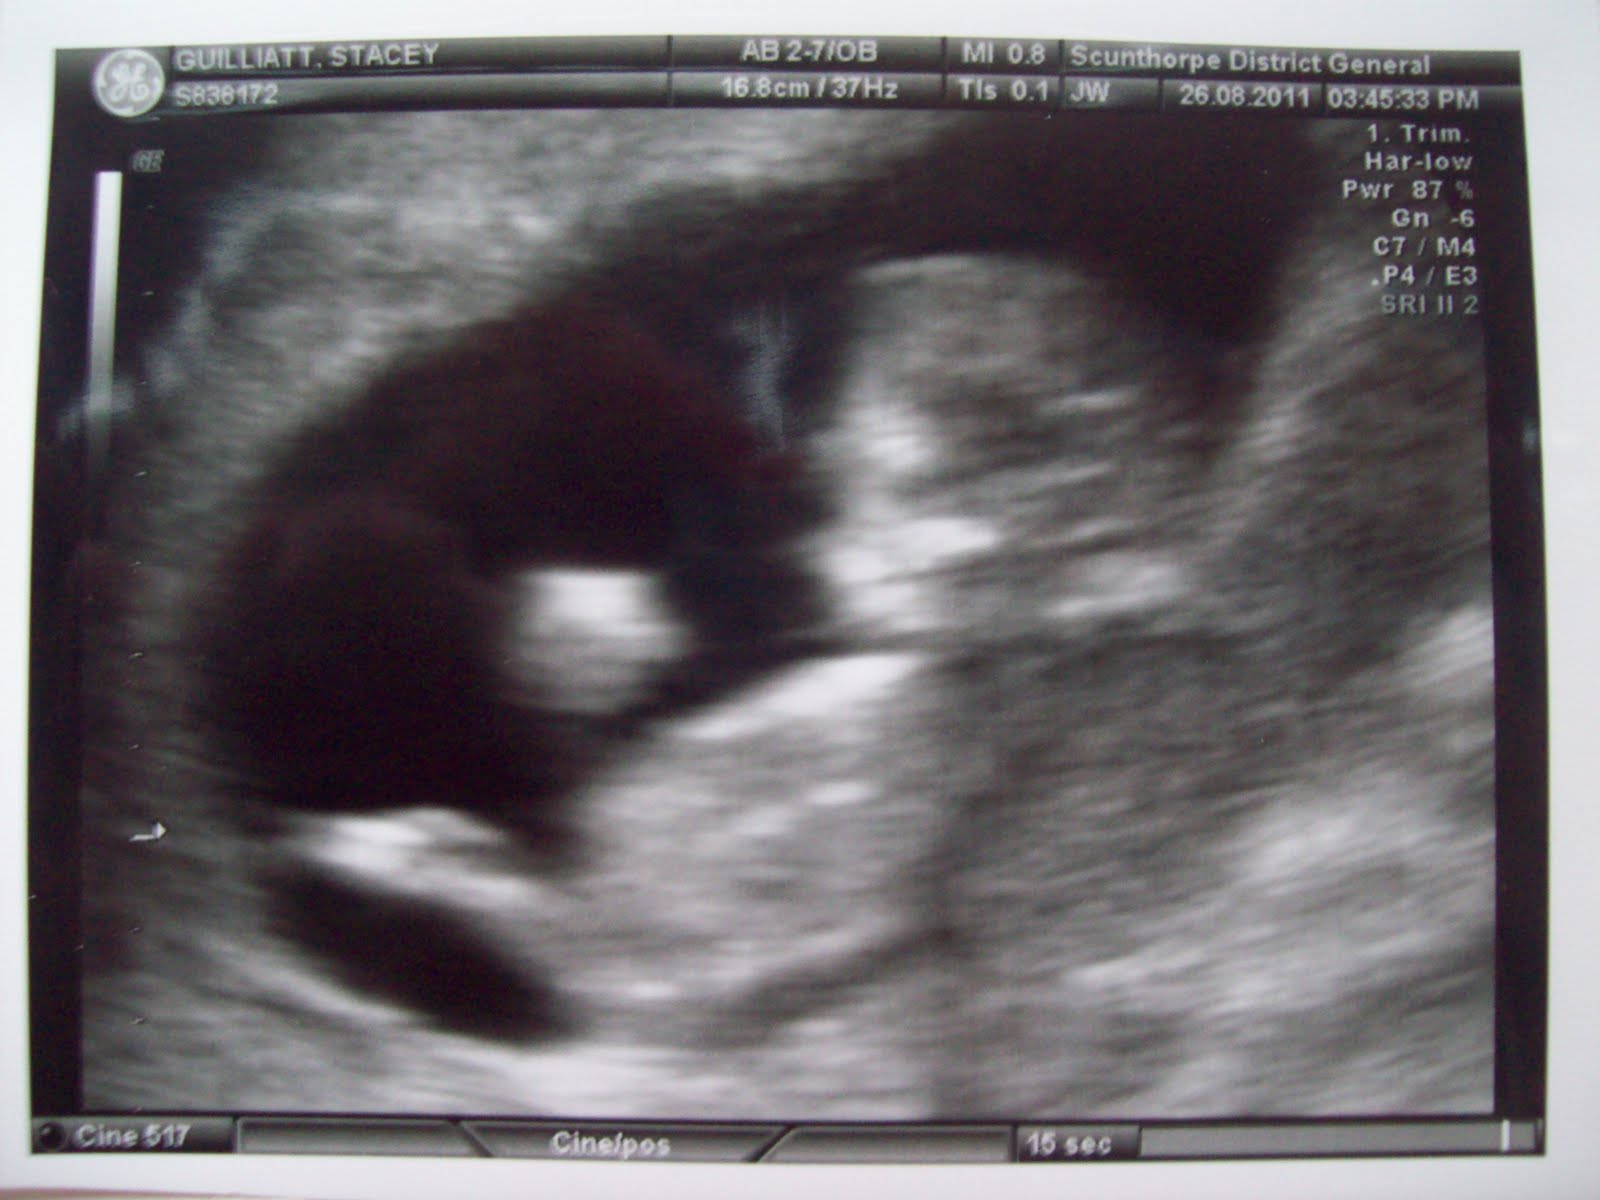

Well, after such a long wait we finally had our very first scan! For 2 years and 8 months we had been waiting for this moment! Not got much more to say as I’m still so excited! I thought I was 12 weeks today, but I’m actually 11+5, so not too far behind! EDD 11th March 2012!

It was jumping about all over the place so this was the best she got! 😀